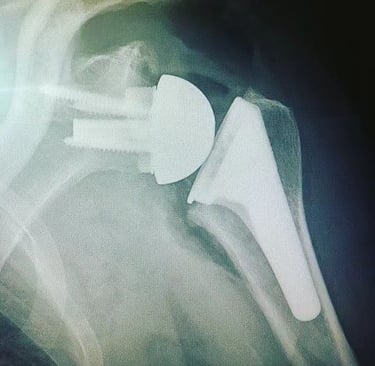

Dans les forme évoluées, ou en cas d'échec du traitement médical, une prothèse totale d'épaule inversée est proposée.

L'intervention consiste a remplacer les surface articuliraire abimer tout en restaurant les mobilités et l'indolence de l'épaule.

La coiffe des rotateurs étant détériorés, l'action du muscle deltoïde est privilégier pour animer l'épaule. Pour ce faire: les surface articulaire sont inversées:

une sphère est placée sur l'omoplate ( 4)

une cupule est placée au sommet de l'humérus ( 5).

Prothèse Totale d'Epaule Inversée